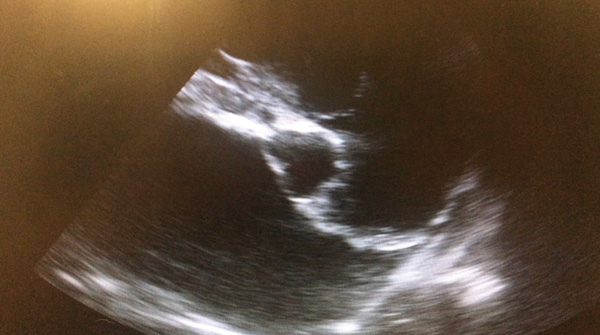

Point-of-care ultrasound is a tool to be used alongside the physical examination in the initial assessment of the dyspnoeic patient. No clipping is required, instead parting the fur and application of spirit to the skin should provide adequate contact for the probe. Placement of the probe in the rib spaces at numerous places dorsally and ventrally in numerous sites on both the left and right hemithorax will allow for assessment of pleural space disease and pulmonary disease. Pleural effusion and pericardial effusions can be identified easily as largely anechoic areas (Figure 3a). However, exudates may appear to be more echogenic. Ultrasound features of lung disease include the presence of ‘B lines’ or 'comet tails’ obliterating the normal ultrasound-gas interference (Figures 3b and 3c) With practice, cardiac chambers and the presence of a ‘glide sign’ can also be assessed on point-of-care ultrasound. Placement of the probe vertically between the ribs on the right hemithorax over the apex heartbeat allows visualisation for the four chamber view and then, with movement of the probe horizontally and cranially, the left atria to aorta ratio can be assessed. This requires practice and care should be taken to ensure correct chambers are identified before attempting a measurement. Increased left atria to aorta ratio suggests cardiac disease as strongly as the case of dyspnoea (Figure 4). A glide sign or ‘sliding lung’ represents the pleural-pulmonary line and in the absence of pleural space disease the lung glides along the thoracic wall as the patient breathes in and out. Absence of this line is suggestive of a pneumothorax.

Figure 4. Enlarged left atrium to aorta

A dyspnoeic dog with a murmur, tachycardia, dyspnoea, B lines and enlarged left atrium to aorta ratio is highly likely to have congestive heart failure. Early use of frusemide may improve the patient’s condition. Therefore, a frusemide trial of 1-2mg/kg intramuscularly or intravenously can be performed. With pulmonary oedema, there should be a decrease in respiratory rate after frusemide therapy when the patient is not stressed. If there is no significant improvement, frusemide can be discontinued. If there is significant improvement, starting a continuous rate infusion of frusemide may be beneficial to minimise the resultant electrolyte disturbances that occur as a consequence of frusemide use.